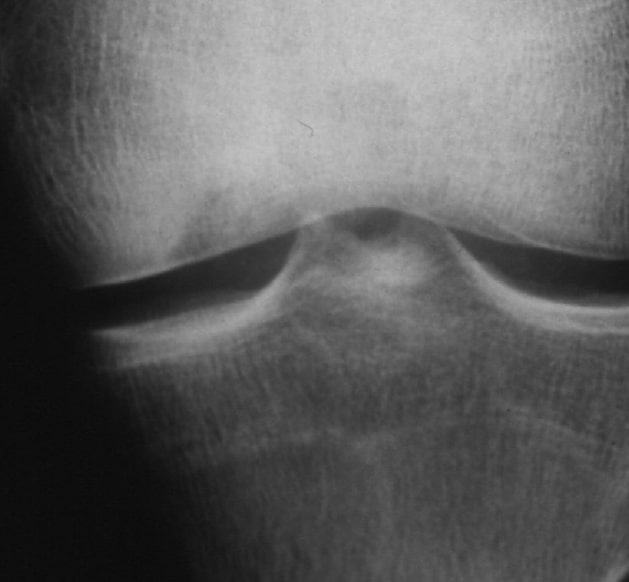

X-ray image preoperatively

Deep osteochondritic defect. Free joint body lies in the mouse bed